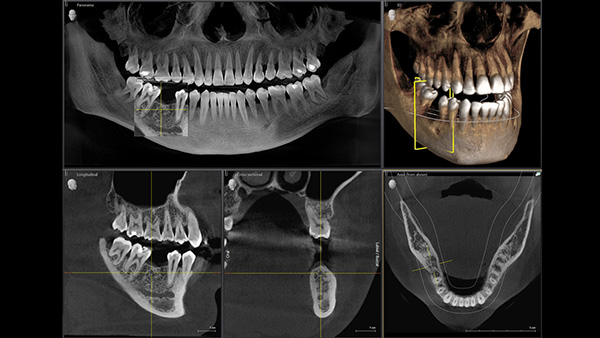

At Pope Family Dentistry we are pleased to offer 3D X-ray technology to our patients. 3D cone beam imaging increases diagnostic accuracy by taking multiple images at different angles of the teeth and jaws. With this advanced technology Dr. Pope can diagnose dental problems at their onset, allowing for early intervention. The process of taking the image only takes around 14 seconds to complete, and the image is available on the computer within minutes. The entire process is comfortable and quick for the patient and the radiation dosage is minimal.